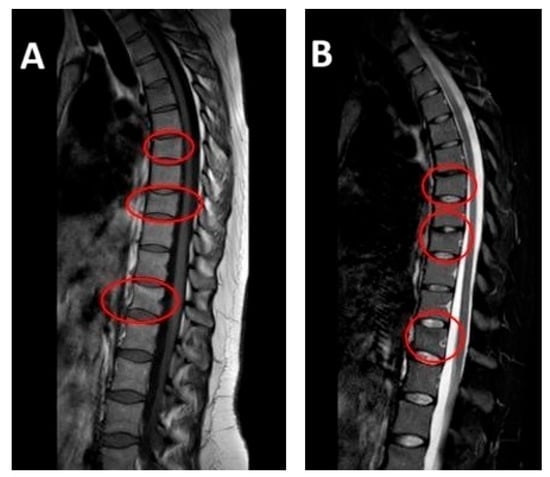

The patient delivered without complications in December 2023. The lower back pain persisted even after delivery. In January 2024, the gynecologist conducted a postpartum follow-up examination due to the patient’s presentation of multiple symptoms, including severe pain. Subsequently, magnetic resonance imaging (MRI) was ordered for further evaluation. The results indicated very slight deformities in the T7, T9, and T12 vertebral bodies due to vertebral fractures located in the disco-somatic regions. There was also a linear edematous band present in the vertebral bodies, along with some depression in the superior limits of T7 and T9, and a slight depression in the inferior limit of T12. No additional pathologies, such as herniations or disc issues, were observed in this MRI (Figure 1). Consequently, the gynecologist referred the patient to the aforementioned Rehabilitation Department. It is important to note that, based on the presence of fractures, the gynecologist recommended avoiding breastfeeding to prevent further worsening of the condition; however, the patient refused to do so. Due to persistent and intensifying pain, the patient was referred to a physiatrist.

Figure 1. MRI at initial diagnosis (January 2024, one month postpartum): MRI (T1—weighted sequence on the (left), T2—weighted sequence on the (right)) showing anterior wedge compression fractures at T7, T9 and T12, with linear bone marrow edema and mild depression of vertebral endplates. No disc herniation or spinal canal narrowing is present.